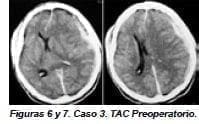

Paciente de 46 años de edad, de sexo masculino quién ingresó al HUFSFB por politraumatismo al ser atropellado por un vehículo, pérdida de la conciencia seguida de rápido deterioro del estado neurológico y dilatación de la pupila izquierda con pérdida del reflejo fotomotor y hemiplejía derecha; fue intubado, sedado, relajado y puesto en respiración mecánica con ventilador.

Se le practicó una TAC cerebral (figuras 6, 7) que se mostró hematoma subdural agudo en hemisferio izquierdo, con desviación de línea media, hernia subfalcina y edema cerebral en hemisferio izquierdo. Llevado inmediatamente a cirugía, se le practicó hemicraniectomía izquierda descomprensiva y ventriculostomía para monitoría de la presión intracraneana (figura 8).